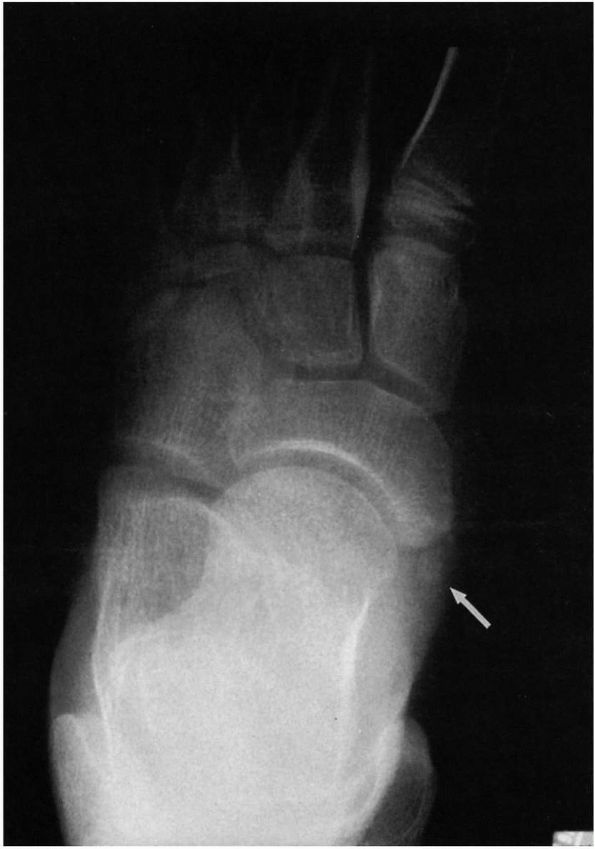

The diagnosis of a calcaneonavicular coalition can usually be made on

these standard radiographs. The 45° medial oblique radiograph usually

demonstrates this coalition. If the coalition is fibrous or

cartilaginous, however, it may not be obvious on plain radiographs.

Other findings that indicate a possible calcaneonavicular coalition

include elongation at the anterior portion of the calcaneus to a point

of close proximity to the navicular and irregular, sclerotic

margins of the two bones in close approximation (see Figure 20-16).

coalitions were often difficult to diagnose. In suspected talocalcaneal

coalitions, Harris views taken from behind the foot at an angle 45°

from the horizontal demonstrate the posterior and medial facets of the

subtalar joint. Normally, these are parallel, but coalitions may be

diagnosed by the loss of the parallel orientation between the two

facets, presence of fusion, or irregular or sclerotic surfaces (see Figure 20-17).